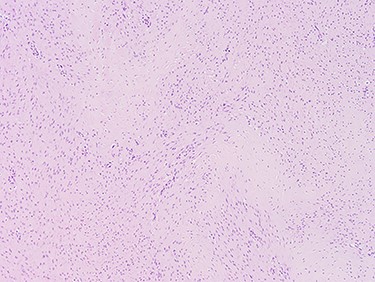

With a radiological diagnosis of LD, the management options were discussed with the patient and her family, who agreed to proceed with surgical excision. A wide local excision was performed; the tissue sent for histopathological analysis, which confirmed the diagnosis of LD (Figs 2 and 3).

Images at ×4 magnification. Tissue samples comprise of cytologically bland spindle cell proliferative features which extends into the adjacent fibrofatty tissue.

The cellular pattern is haphazard with areas of dense fibrosis, suggestive of fibromatosis (LD).